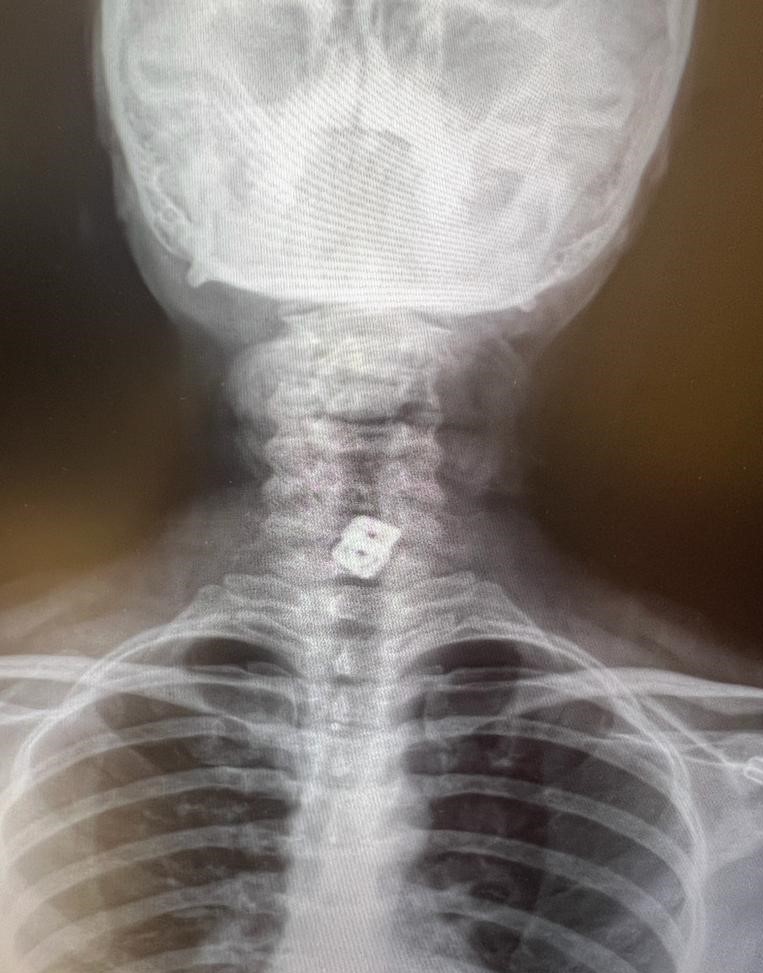

Sultan Tıraş’ın Gaziantep’te başka özel hastanede yapılan radyolojik tetkikler ve değerlendirmeler sonucu daha önce başka bir merkezde boyun omurlarına yerleştirilen metal disklerin yerinden oynadığının saptandığını anımsatan Prof. Dr. Elbeyli, sözlerini şöyle sürdürdü:

“O hastanede beyin ve sinir cerrahisi uzmanı tarafından ameliyata alınan Sultan Tıraş’ın boyun omuruna konulan iki aparattan biri çıkarılmış, ancak diğerinin yemek borusunu delip mideye indiği belirlenmiş. İlgili hekim bana ulaşarak bilgilendirmeyi yaptı ve hastayı hastanemize sevk etti.

Yoğun bakıma alınan hastaya yaptığımız detaylı tetkikler ve klinik değerlendirme sonucu mediyastenit (ciddi göğüs enfeksiyonu) saptandı. Bu ciddi bir sorun olup, hayati riski yüksektir. En hızlı şekilde tıbbi tedaviye başladık, gastroenteroloji bölümümüzde endoskopi yapıldı.

Yemek borusunda oluşan delik ve delikten mideye inen metalik cerrahi aparat görüldü. Göğüs kafesi içinde ciddi bir iltihap ve hava birikimi vardı. Hasta yakınları durum ile ilgili bilgilendirildi, riskler kendileri ile paylaşılarak hastamıza tıbbi müdahale edebilmemiz gerekli onayları alındı.”